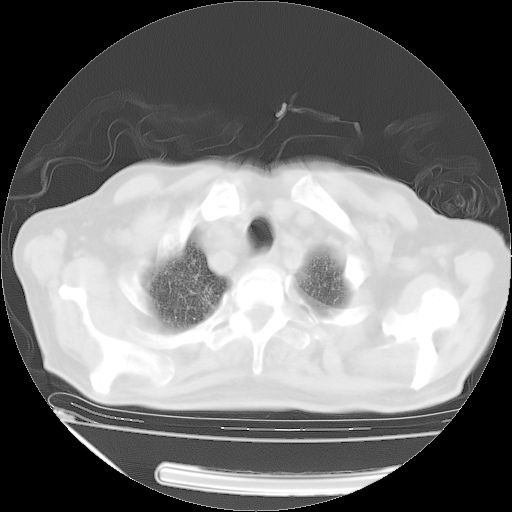

经过24天治疗,岳父的病情基本稳定。生活基本可以自理,可以下床活动。呼吸困难早已消失。体温基本正常。

主要治疗甲强龙80mg×14天,60mg×10天;同时抗结核(异烟肼+利福平+乙胺丁醇)。环磷酰胺0.1 tid 10天。

特别感谢胡教授、高管、桃子版主给出关键的治疗建议。桃版把所有肺部影像和全部临床资料请所在医院呼吸科、感染病科、结核科、临床免疫科专家会诊。临床免疫科专家制定了完整的治疗方案。